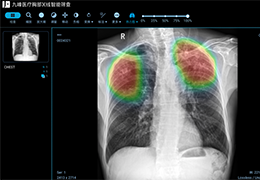

成像智能。

Eclipse 成像智能功能提供强大的处理能力和最佳质量的影像,同时减少质量错误并提高剂量效率。

凭借 AI、专有算法和先进的影像处理能力,提供出色的影像质量和无与伦比的诊断信心。

与标准影像处理相比,智能降噪功能可使客户降低辐射剂量,而不会损失影像质量。这在新生儿和儿科成像中尤其重要,在这种情况下以尽可能低的剂量成像至关重要。

提供相配视图选项,以减少所需的曝光次数,并提供更清晰的感兴趣区域视图。